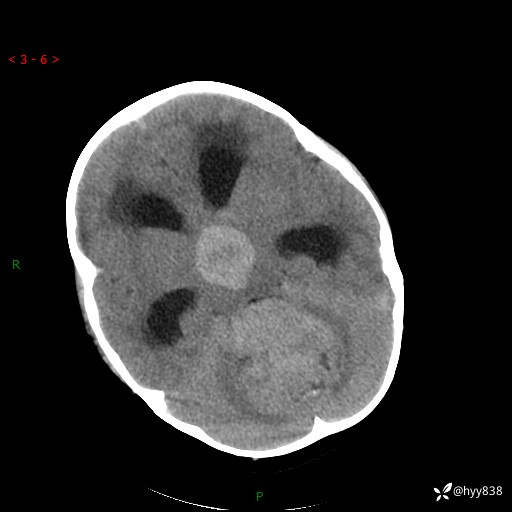

颅脑CT平扫

三脑室、四脑室多发病变,如何分析?

髓母细胞瘤 (13)